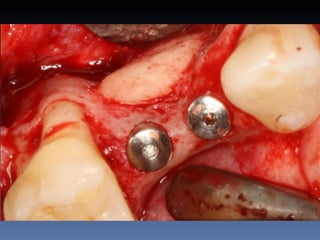

BOX 3

José Luiz Peretti

Idade – 67 anos

Sexo – Masculino

Raça – Caucasiana

ASA – II

Data- 23-04-2012

Diagnóstico: Desdentado parcial maxila

Plano de tratamento: Reabilitação da área desdentada

1.4,.1.5 com instalação de 2 implantes endo-ósseos

para reabilitação protética fixa .

O meu primeiro Implante